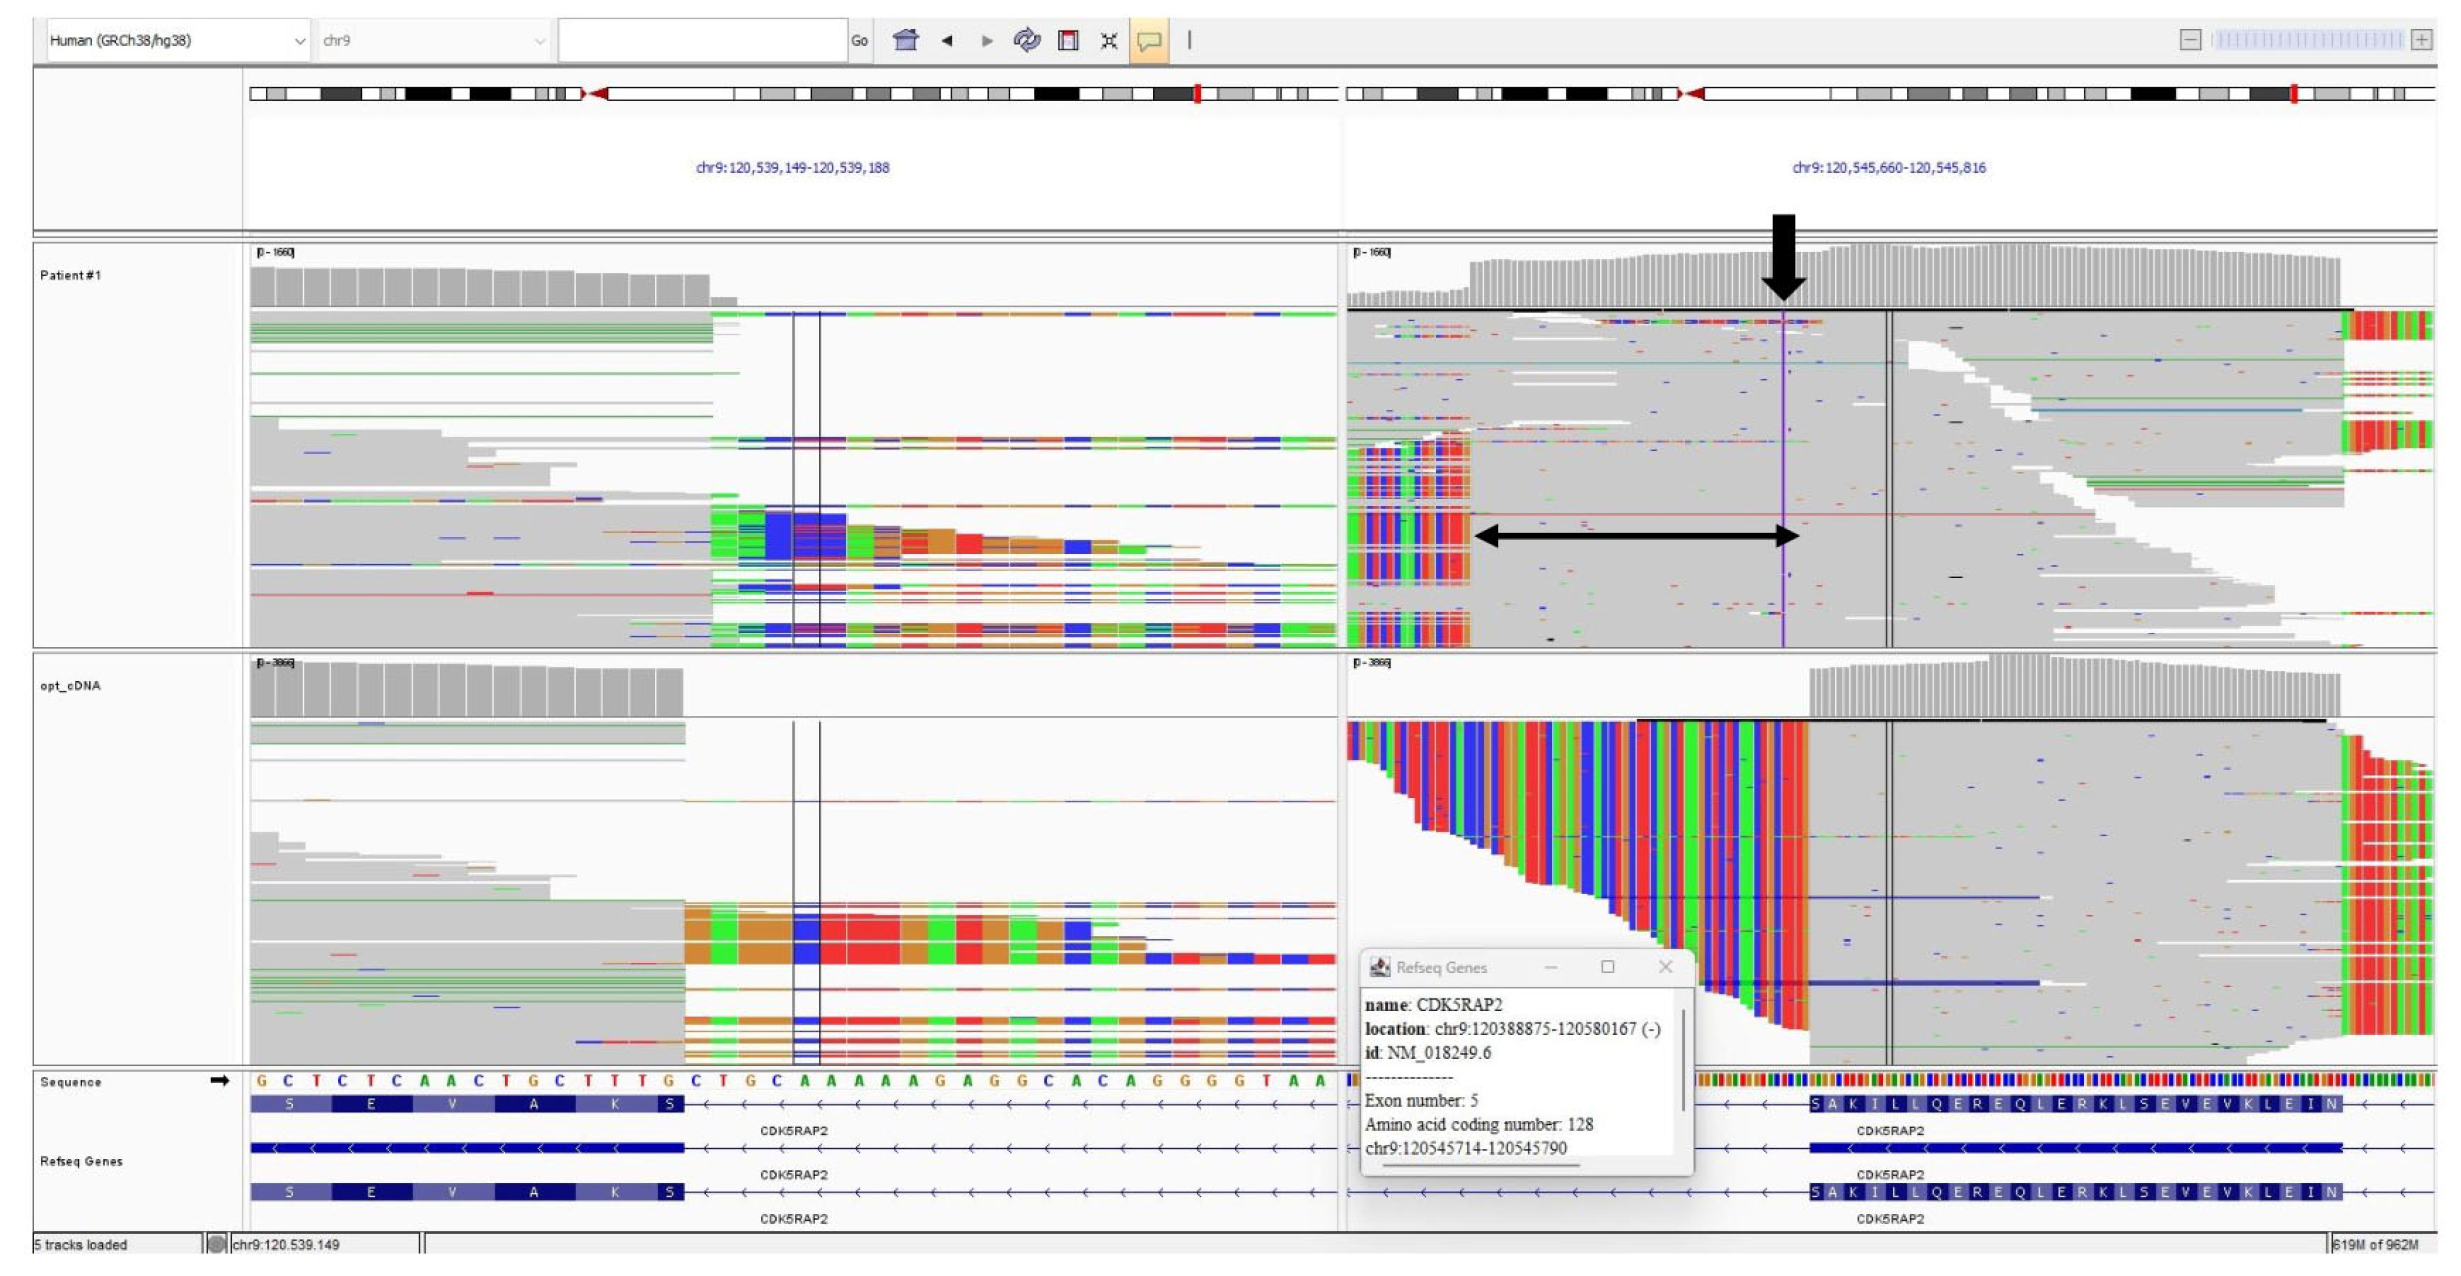

3.3. CDK5RAP2 Variants

3.4. cDNA Analysis

| CDK5RAP2 homozygous variant (NM_018249.6) | c.3148+5G>C | c.383+4dupA | c.3168del (p.Asp1057Metfs*17) | c.3168del (p.Asp1057Metfs*17) | c.1591C>T (p.Gln531*) | c.1591C>T (p.Gln531*) | c.1296dup (p.Asp433Argfs*6) |

| Variant type | Intronic | Intronic | Frameshift | Frameshift | Nonsense | Nonsense | Frameshift |